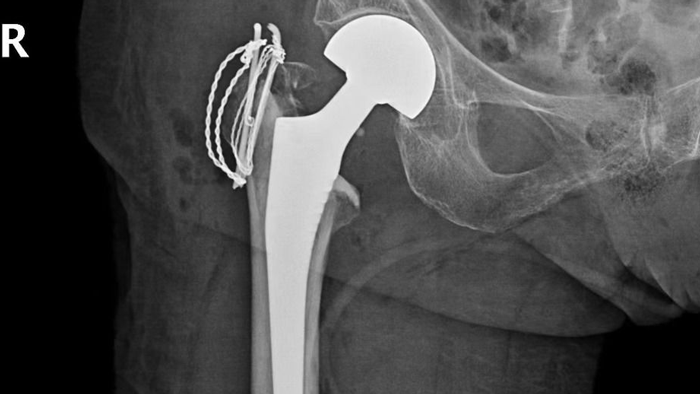

考虑到患者高龄,情况复杂,骨外科主任黄超带领科室医护团队迅速联合呼吸内科、神经内科、心内科、麻醉科等相关科室进行会诊,各科室共同完成患者的身体评估后,为尽快解除患者的病痛,避免诱发更多并发症,于2月6日为患者实施右侧半髋关节置换术,在各科室的紧密配合下,手术一切顺利。

术后